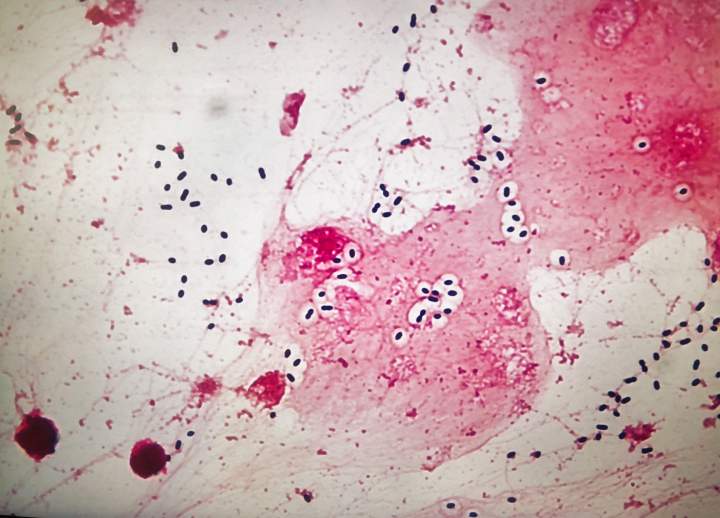

Actor Daveigh Chase is dead at 35 after meningitis. What is it?The Centers for Disease Control and Prevention (CDC) defines meningitis as "inflammation (swelling) of the lining of the brain and spinal cord."HealthJun 18